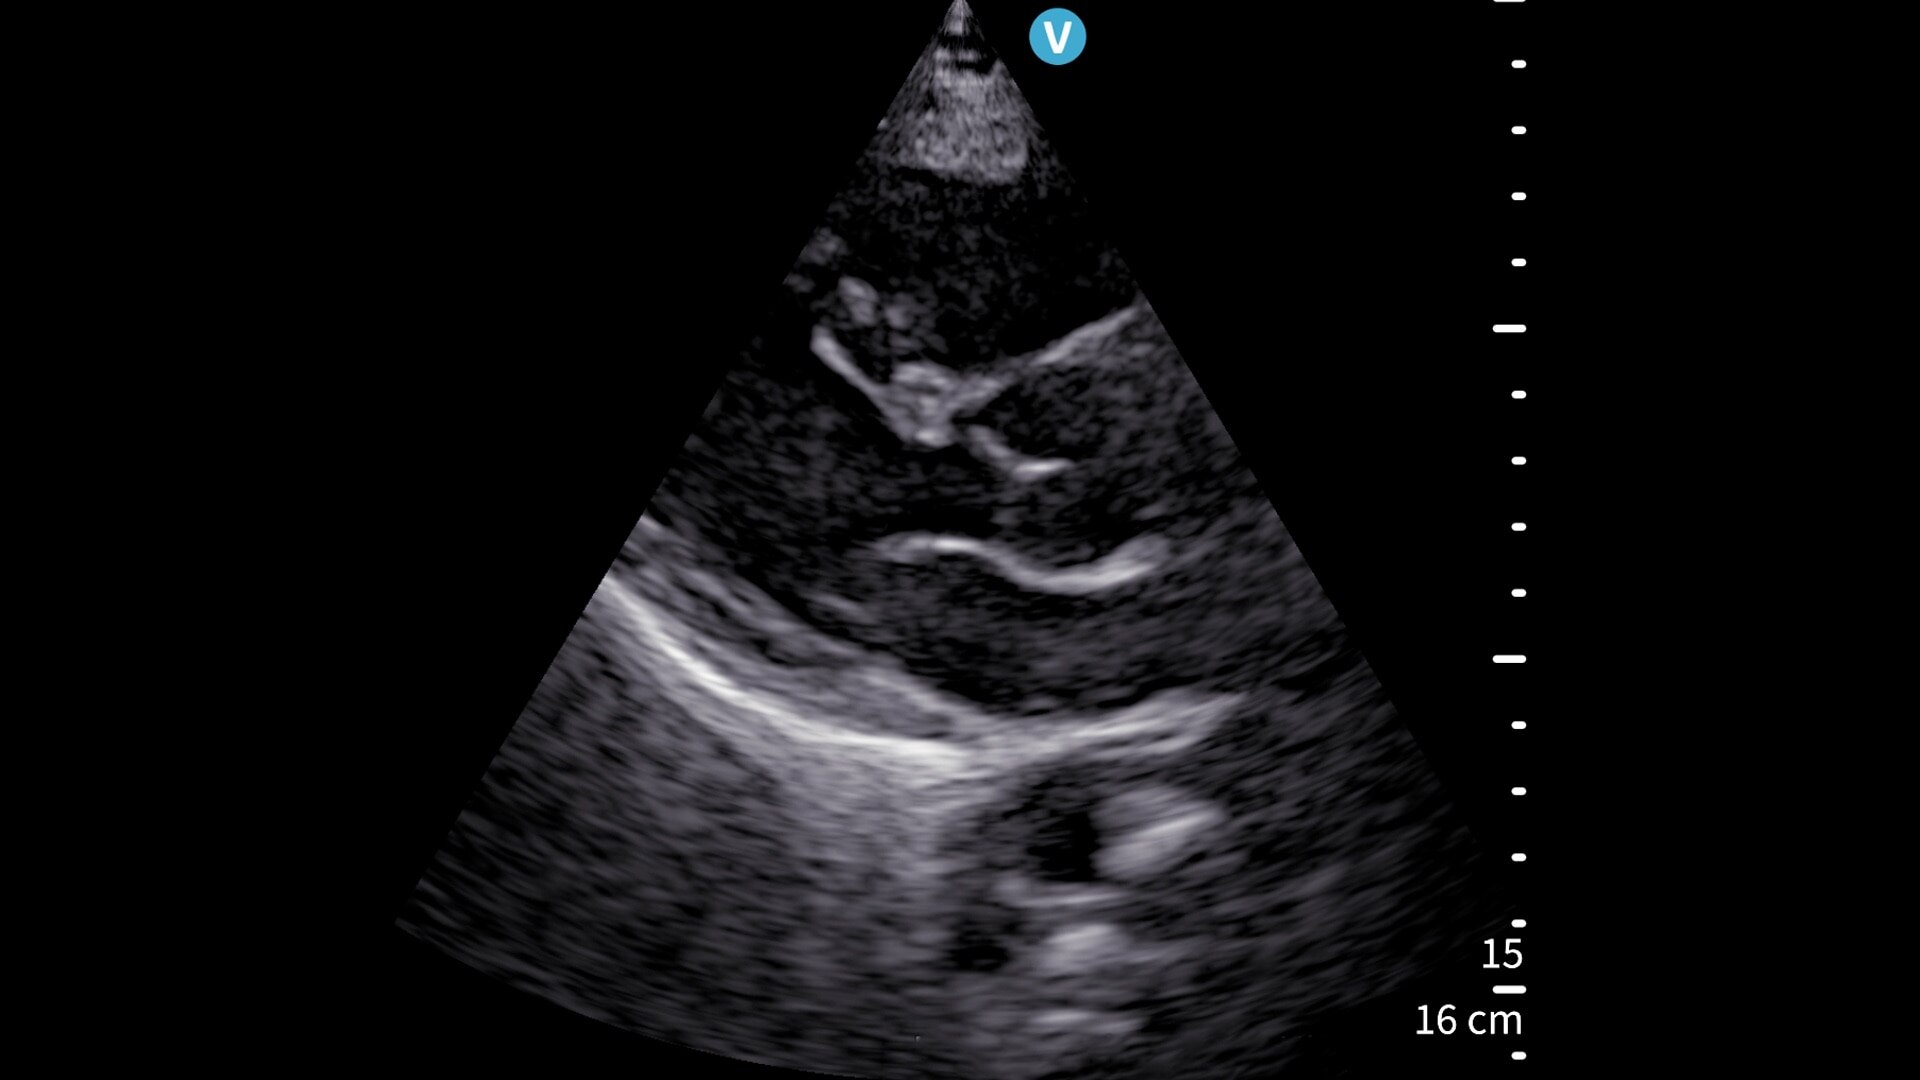

Vscan Air SL is a wireless, handheld ultrasound system that delivers crystal-clear images and is well-suited for rapid cardiac and vascular assessments.

Don’t miss a beat between cardiac, vascular, and other evaluations

Vscan Air SL handheld ultrasound offers wireless freedom and maximum portability with two transducers in a single device. Delivers crystal-clear images at the point of care. Sector-phased array transducer is ideal for rapid cardiac assessments. The linear array transducer allows you to move from a cardiac to a vascular assessment without missing a beat.

Image quality you can be confident in

With our proprietary SignalMax™ + XDclear™ technology, GE HealthCare sets a new standard in handheld ultrasound, delivering extraordinary image quality with our sector phased array transducer. Combining SignalMax high-intensity signal processing and single crystal transducer technology, it ensures exceptional penetration, resolution, and sensitivity. Vscan Air also uses High-Definition Speckle Reduction Imaging (HD-SRI) to further enhance image quality with optimized contrast resolution and a smoother appearance to enhance details.